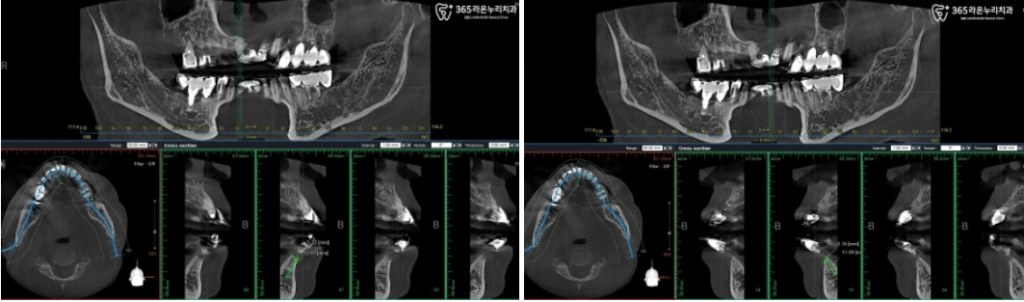

수술 전 ct 촬영을 통해

해당 부위의 상태를 파악하고

정확한 계획을 세우는데

많은 도움을 받을 수 있습니다.

아래 앞니 브릿지 제작을 위해

두 개의 임플란트 픽스처를

의도한 곳에 잘 식립한 모습입니다.